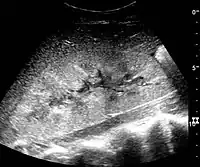

In medical imaging, the acute changes in the kidney are often examined with renal ultrasonography as the first-line modality, where CT scan and magnetic resonance imaging (MRI) are used for the follow-up examinations and when US fails to demonstrate abnormalities. In evaluation of the acute changes in the kidney, the echogenicity of the renal structures, the delineation of the kidney, the renal vascularity, kidney size and focal abnormalities are observed.[16] CT is preferred in renal traumas, but US is used for follow-up, especially in the patients suspected for the formation of urinomas. A CT scan of the abdomen will also demonstrate bladder distension or hydronephrosis.

Renal ultrasonograph in renal failure after surgery with increased cortical echogenicity and kidney size. Biopsy showed acute tubular necrosis.[16]